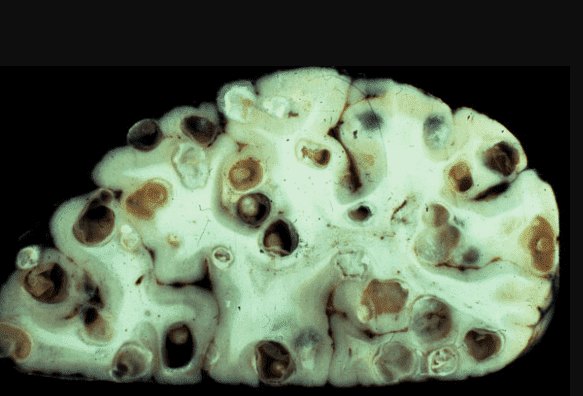

Мозок, уражений паразитами

Ще одна недавня історія. Пацієнтка померла від раку кишківника, спричиненого паразитами. Паразити отруюють здорові клітини своїми токсинами, через що вони змушені перероджуватися, змінювати свою структуру. І перероджуються вони саме в ракові клітини, які агресивніші й здатні протистояти паразитам. Але для людини ці клітини згубні. Пухлина швидко розвивається і пускає метастази. Людина гине протягом лічених місяців.

На фото нижче можете побачити знімок кишечника. Пацієнтка померла від раку кишківника, спричиненого паразитами. Паразити отруюють здорові клітини своїми токсинами, через що вони змушені перероджуватися, змінювати свою структуру. І перероджуються вони саме в ракові клітини, які агресивніші й здатні протистояти паразитам. Але для людини ці клітини згубні. Пухлина швидко розвивається і метастазує. Людина гине протягом лічених місяців.